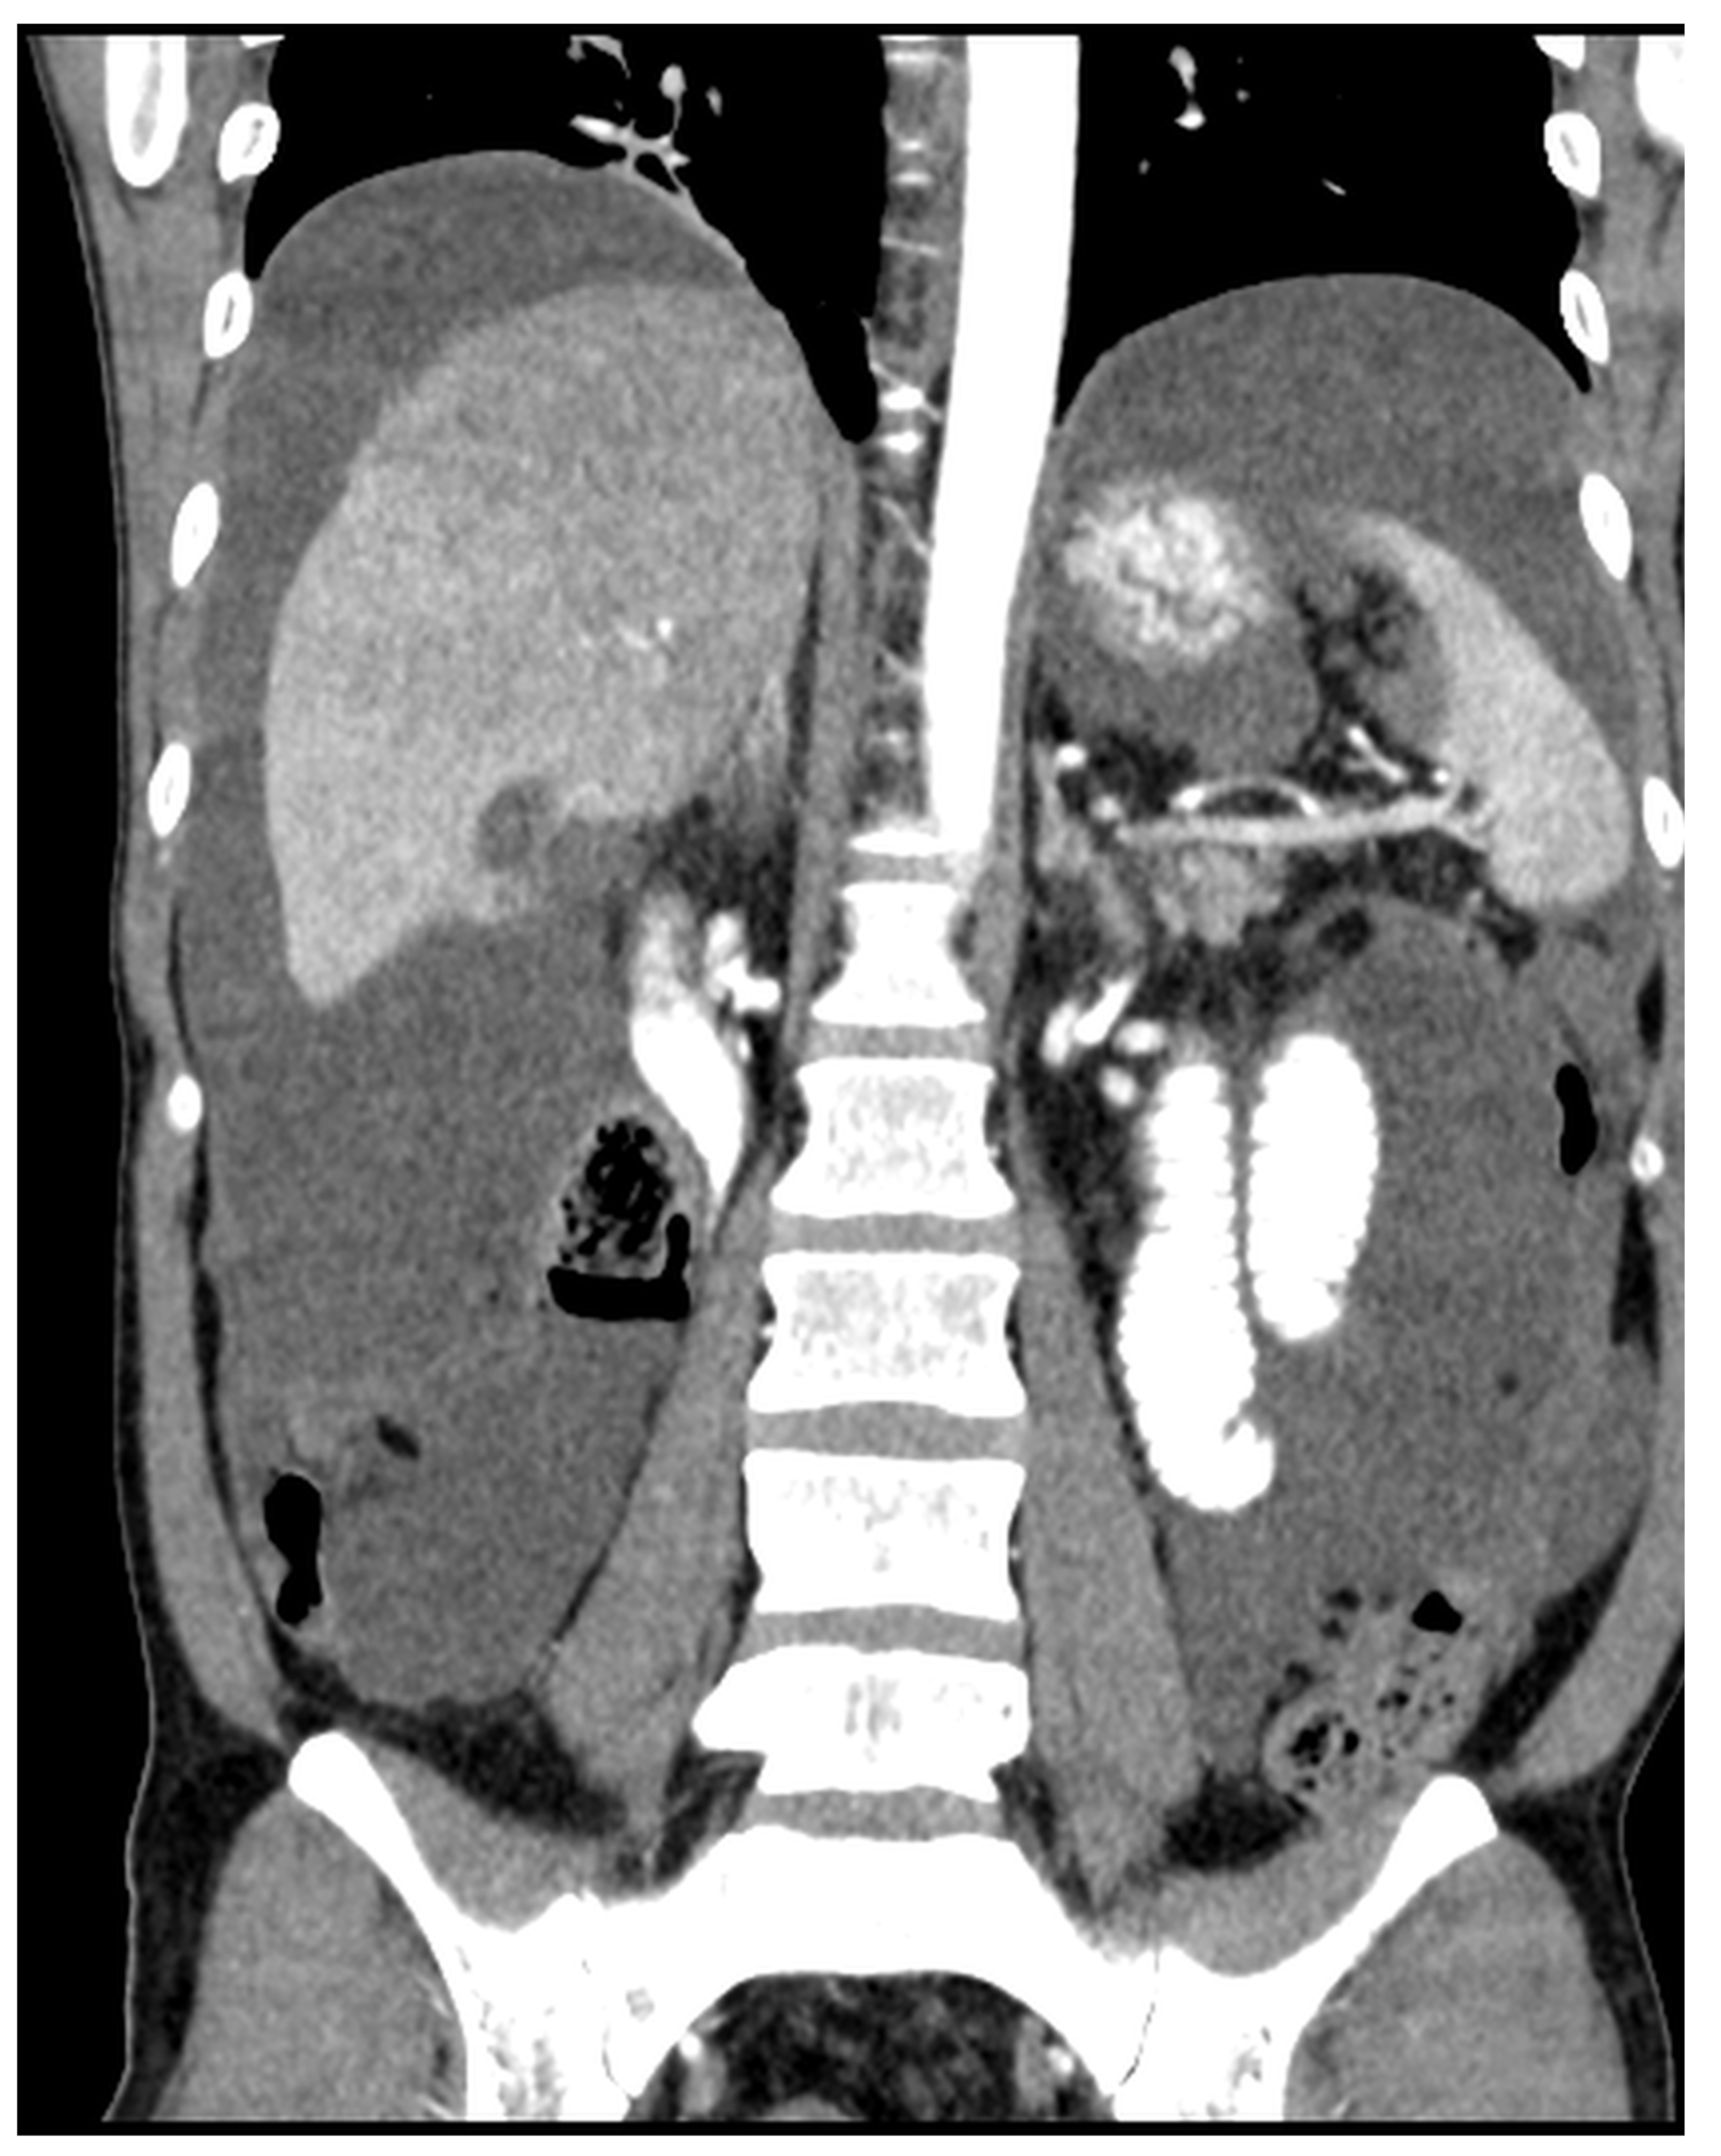

Patients with a misdiagnosed rupture of the mucocele may develop pseudomyxoma peritonei. It is characterized by the presence of an abundant gelatinous substance in the abdomen. Diffuse, progressive, and abundant mucin-containing tumor cells are typical of this disease [2] (Figure 11, Figure 12, Figure 13, Figure 14, Figure 15 and Figure 16). The interval between rupture and advanced disease is several years. In our clinical series, the interval was about 5 years. In the literature, we found a wide range of this interval from 12 months to 10 years [9,10]. The natural history of PMP revolves around the “redistribution phenomenon”, whereby mucinous tumor cells accumulate in the Douglas pouch, in the diaphragm (more on the right), and the small and large omentum (Figure 17). The small intestine is less involved [4]. Pseudomyxoma peritonei is a slowly progressing disease, which fills the peritoneal cavity over time. There are several classifications of pseudomyxoma. The most commonly used is the PSOGI classification [2]. Mucinous accumulation progresses to malnutrition, bowel obstruction, and respiratory compromise. Rarely, the tumor may spread to the pleural cavity. This has been described in 5.4% of cases. It may occur spontaneously or as a result of diaphragmatic injury during cytoreduction [8,11].

Figure 11, Figure 12, Figure 13, Figure 14 and Figure 15. Advanced stage of the disease. The abdomen is full of tumors and mucin. Typical signs are heterogeneous or hypodense masses in the form of lobules often with septa, which could be enhanced by contrast and could be associated with calcifications.

Figure 12. CT, venous phase, coronar plane.